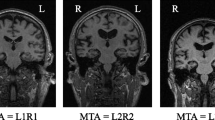

Alzheimer’s disease (AD) is a latent progressive neurodegenerative disease. Early detection can prevent further damage to patient’s health. We proposed a 3D abnormal perception depth residual network based on the squeeze and excitation module (RSE) and recurrent slice attention module (RSA). In our model, RSE captures the importance of different channels by integrating extrusion and excitation modules into residual blocks, while RSA aims to model 3D MRI images as slice sequences to capture the long-term dependence of different slices in different directions. Our model combine the context information of the abnormal area with local and spatial information. Experimental results show that the accuracy of our method is 87.5%, which is better than the most advanced model in terms of normal cognition (NC), early mild cognitive impairment (EMCI), late mild cognitive impairment (LMCI) and Alzheimer’s disease (AD) on the ADNI dataset. The CAM visualization results also show that our method can successfully highlight the most contributing regions of 3D MRI images.